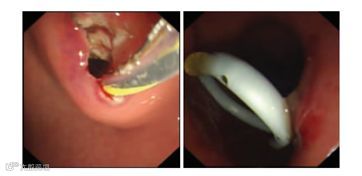

超声内镜下可见支架推送装置

支架释放效果